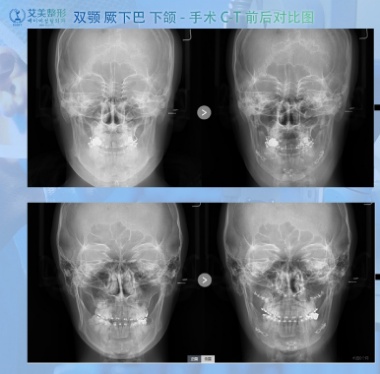

Page 60 - 艾美综合整形_Neat